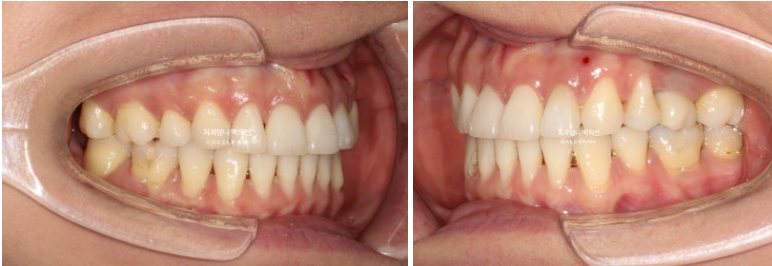

23년 8월, 재교정치료를 위해 내원한 환자분입니다.

블랙트라이앵글과 중심선 불일치가 보입니다.

잇몸이 얇은 편이라 작은어금니 부분에 잇몸퇴축도 보입니다.

얼굴에 비해 위 앞니 중심선이 좌측으로 돌아간 상태인데

원인은 좌우 치아 갯수 차이에 있었습니다.

오래 전 했던 발치교정으로 작은어금니 4개가 없는 상태인데 좌측 첫번째 큰어금니 1개가 추가로 더 없습니다.

상악 좌측에만 치아갯수가 2개나 없는거죠.

어금니 교합관계 2급 입니다.